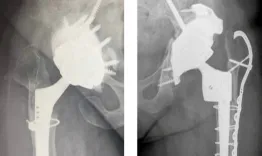

A 71-year-old male, who underwent a right Total Hip Arthroplasty (THA) 12 years ago and a left THA 5 years ago for hip osteoarthritis, recently experienced a fall while walking.

Management of a peri prostetic femoral fracture